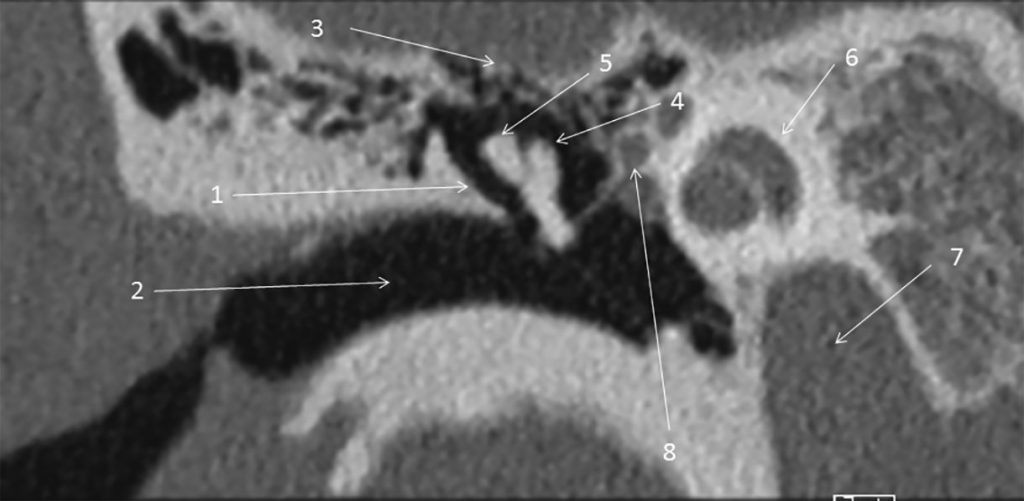

Fig. 62.3 Temporal droit : scanner, coupe frontale.

1. Paroi osseuse latérale du récessus épitympanique. 2. Méat acoustique externe. 3. Tegmen tympani. 4. Tête du malléus. 5. Incus. 6. Cochlée. 7. Canal carotidien. 8. Nerf facial, 2e portion. 9. Cellules mastoïdiennes.

Source : CERF, CNEBMN, 2022.